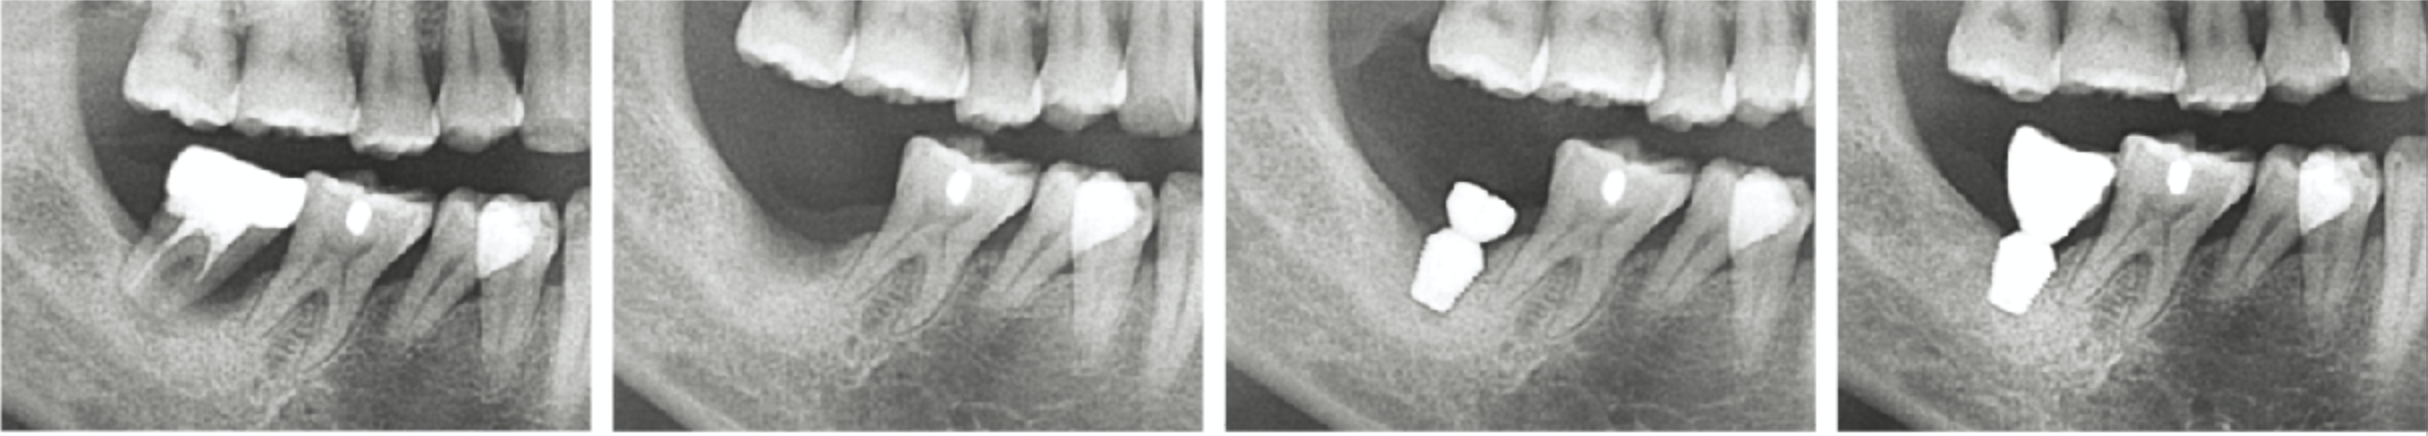

即刻種植也可獲得良好的骨反應(yīng)